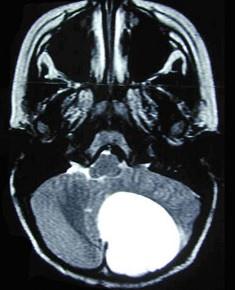

后颅窝脑肿瘤(如图所示)可出现下列症状与体征,但不出现()A.颈项强直B.剧烈头痛C.运动性失语D.共济障碍E.视神经孔扩大

问题 后颅窝脑肿瘤(如图所示)可出现下列症状与体征,但不出现()

选项 A.颈项强直 B.剧烈头痛 C.运动性失语 D.共济障碍 E.视神经孔扩大

答案 C